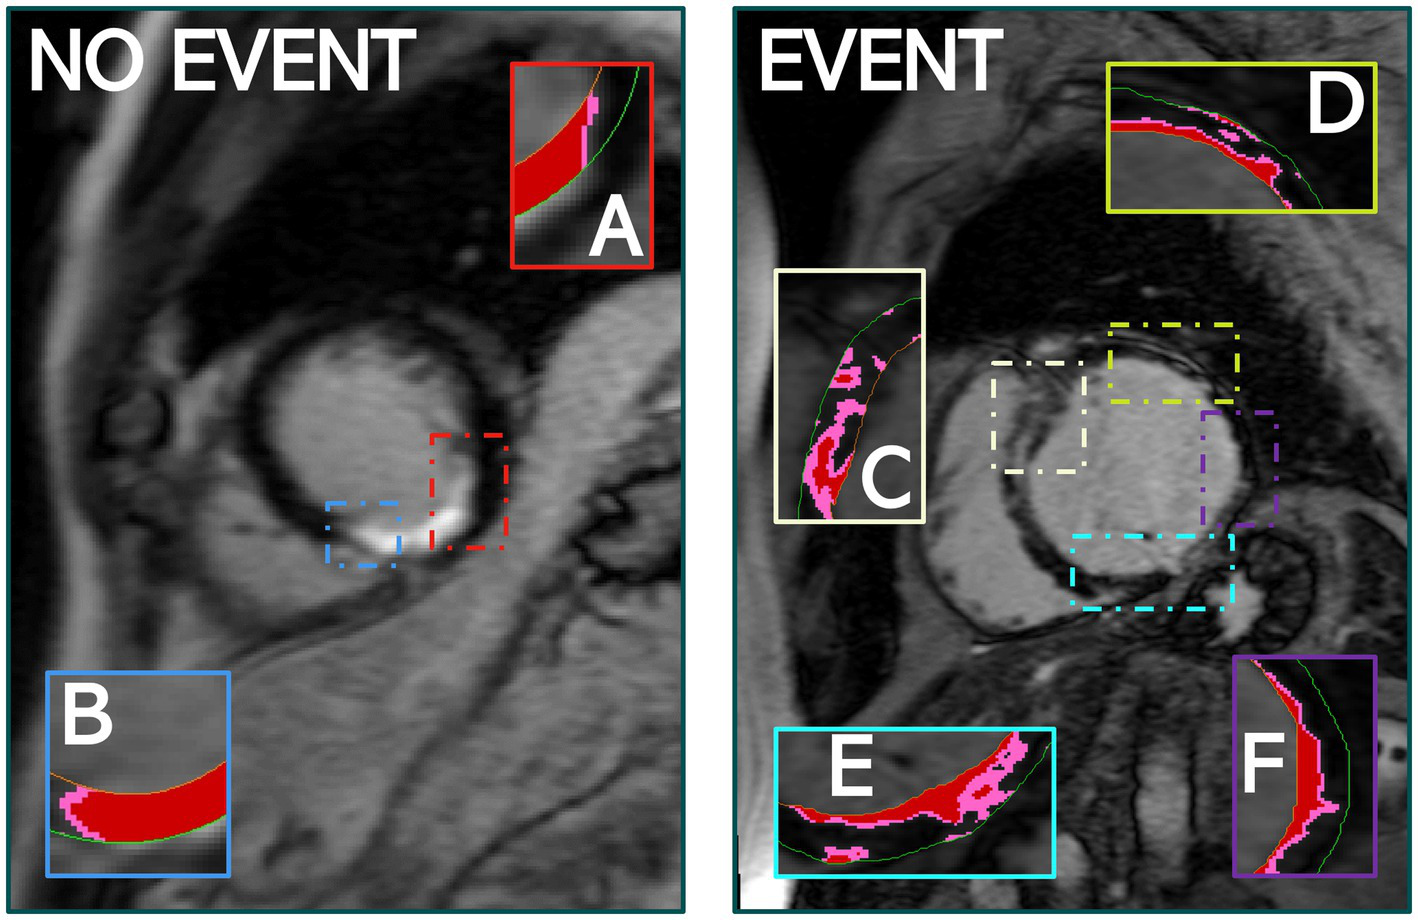

The number of PIZ components details the unique number of PIZ elements across the LV. Our ML analysis consistently demonstrated that the number of PIZ components had important prognostic value in predicting MAE (Figure 5). This result continues to build on the hypothesis that these regions contain the arrhythmogenic substrate needed to initiate and maintain ventricular arrhythmia (23–25).

Figure 5

The quantity of PIZ components was significantly higher in patients that experienced MAE compared to those that did not, as seen above. (A,B) Identify PIZ components, shown in pink with core infarct in red, in a patient who did not experience MAE. (C–F) Show the variety and additional PIZ components in a patient who experienced MAE. Images used FWHM quantification.